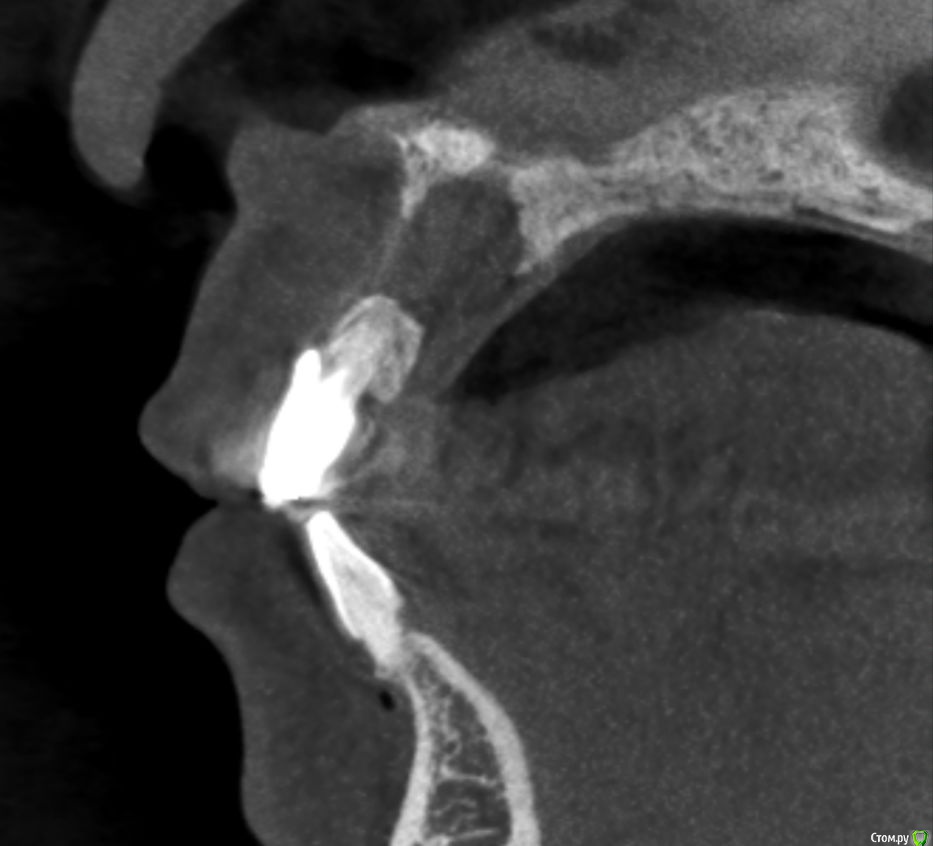

Kazankov.Egor Опубликовано 6 июля, 2018 Поделиться Опубликовано 6 июля, 2018 (изменено) Жалобы на неприятный запах изо рта, предположительно от 11 зуба. В анамнезе РВК 11 зуба.Скрины кт прилагаю. Пациент девушка, естественно, главный вопрос -эстетика. Нужна помощь по тактике. Изменено 6 июля, 2018 пользователем Kazankov.Egor Ссылка на комментарий

Kazankov.Egor Опубликовано 7 июля, 2018 Автор Поделиться Опубликовано 7 июля, 2018 Если зуб под коронкой не сгнил, то ревизия периапикальных тканей и ретроградная пломбировка канала.А с кистой несонобного канала как поступить? Ссылка на комментарий

Kazankov.Egor Опубликовано 7 июля, 2018 Автор Поделиться Опубликовано 7 июля, 2018 При такой тактике не потеряю ли я объем в области кисты? Если сыпать графт, не будет ли повышенного риска его инфицирования? Нужно стабилизировать графт мембраной? Ссылка на комментарий

АнтонТЛТ Опубликовано 7 июля, 2018 Поделиться Опубликовано 7 июля, 2018 Я графт не использую при резекциях. Само восстановится. 1 Ссылка на комментарий